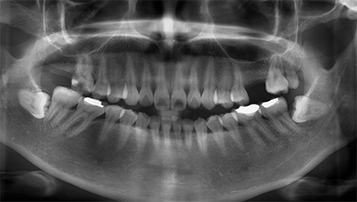

진단 및 치료 계획

파노라마, X-ray, 3D CT 등으로 상태를 면밀하게 진단 후 치료계획을 세웁니다.

W Dental Clinic Before & After

치료 전후사진

Before

After